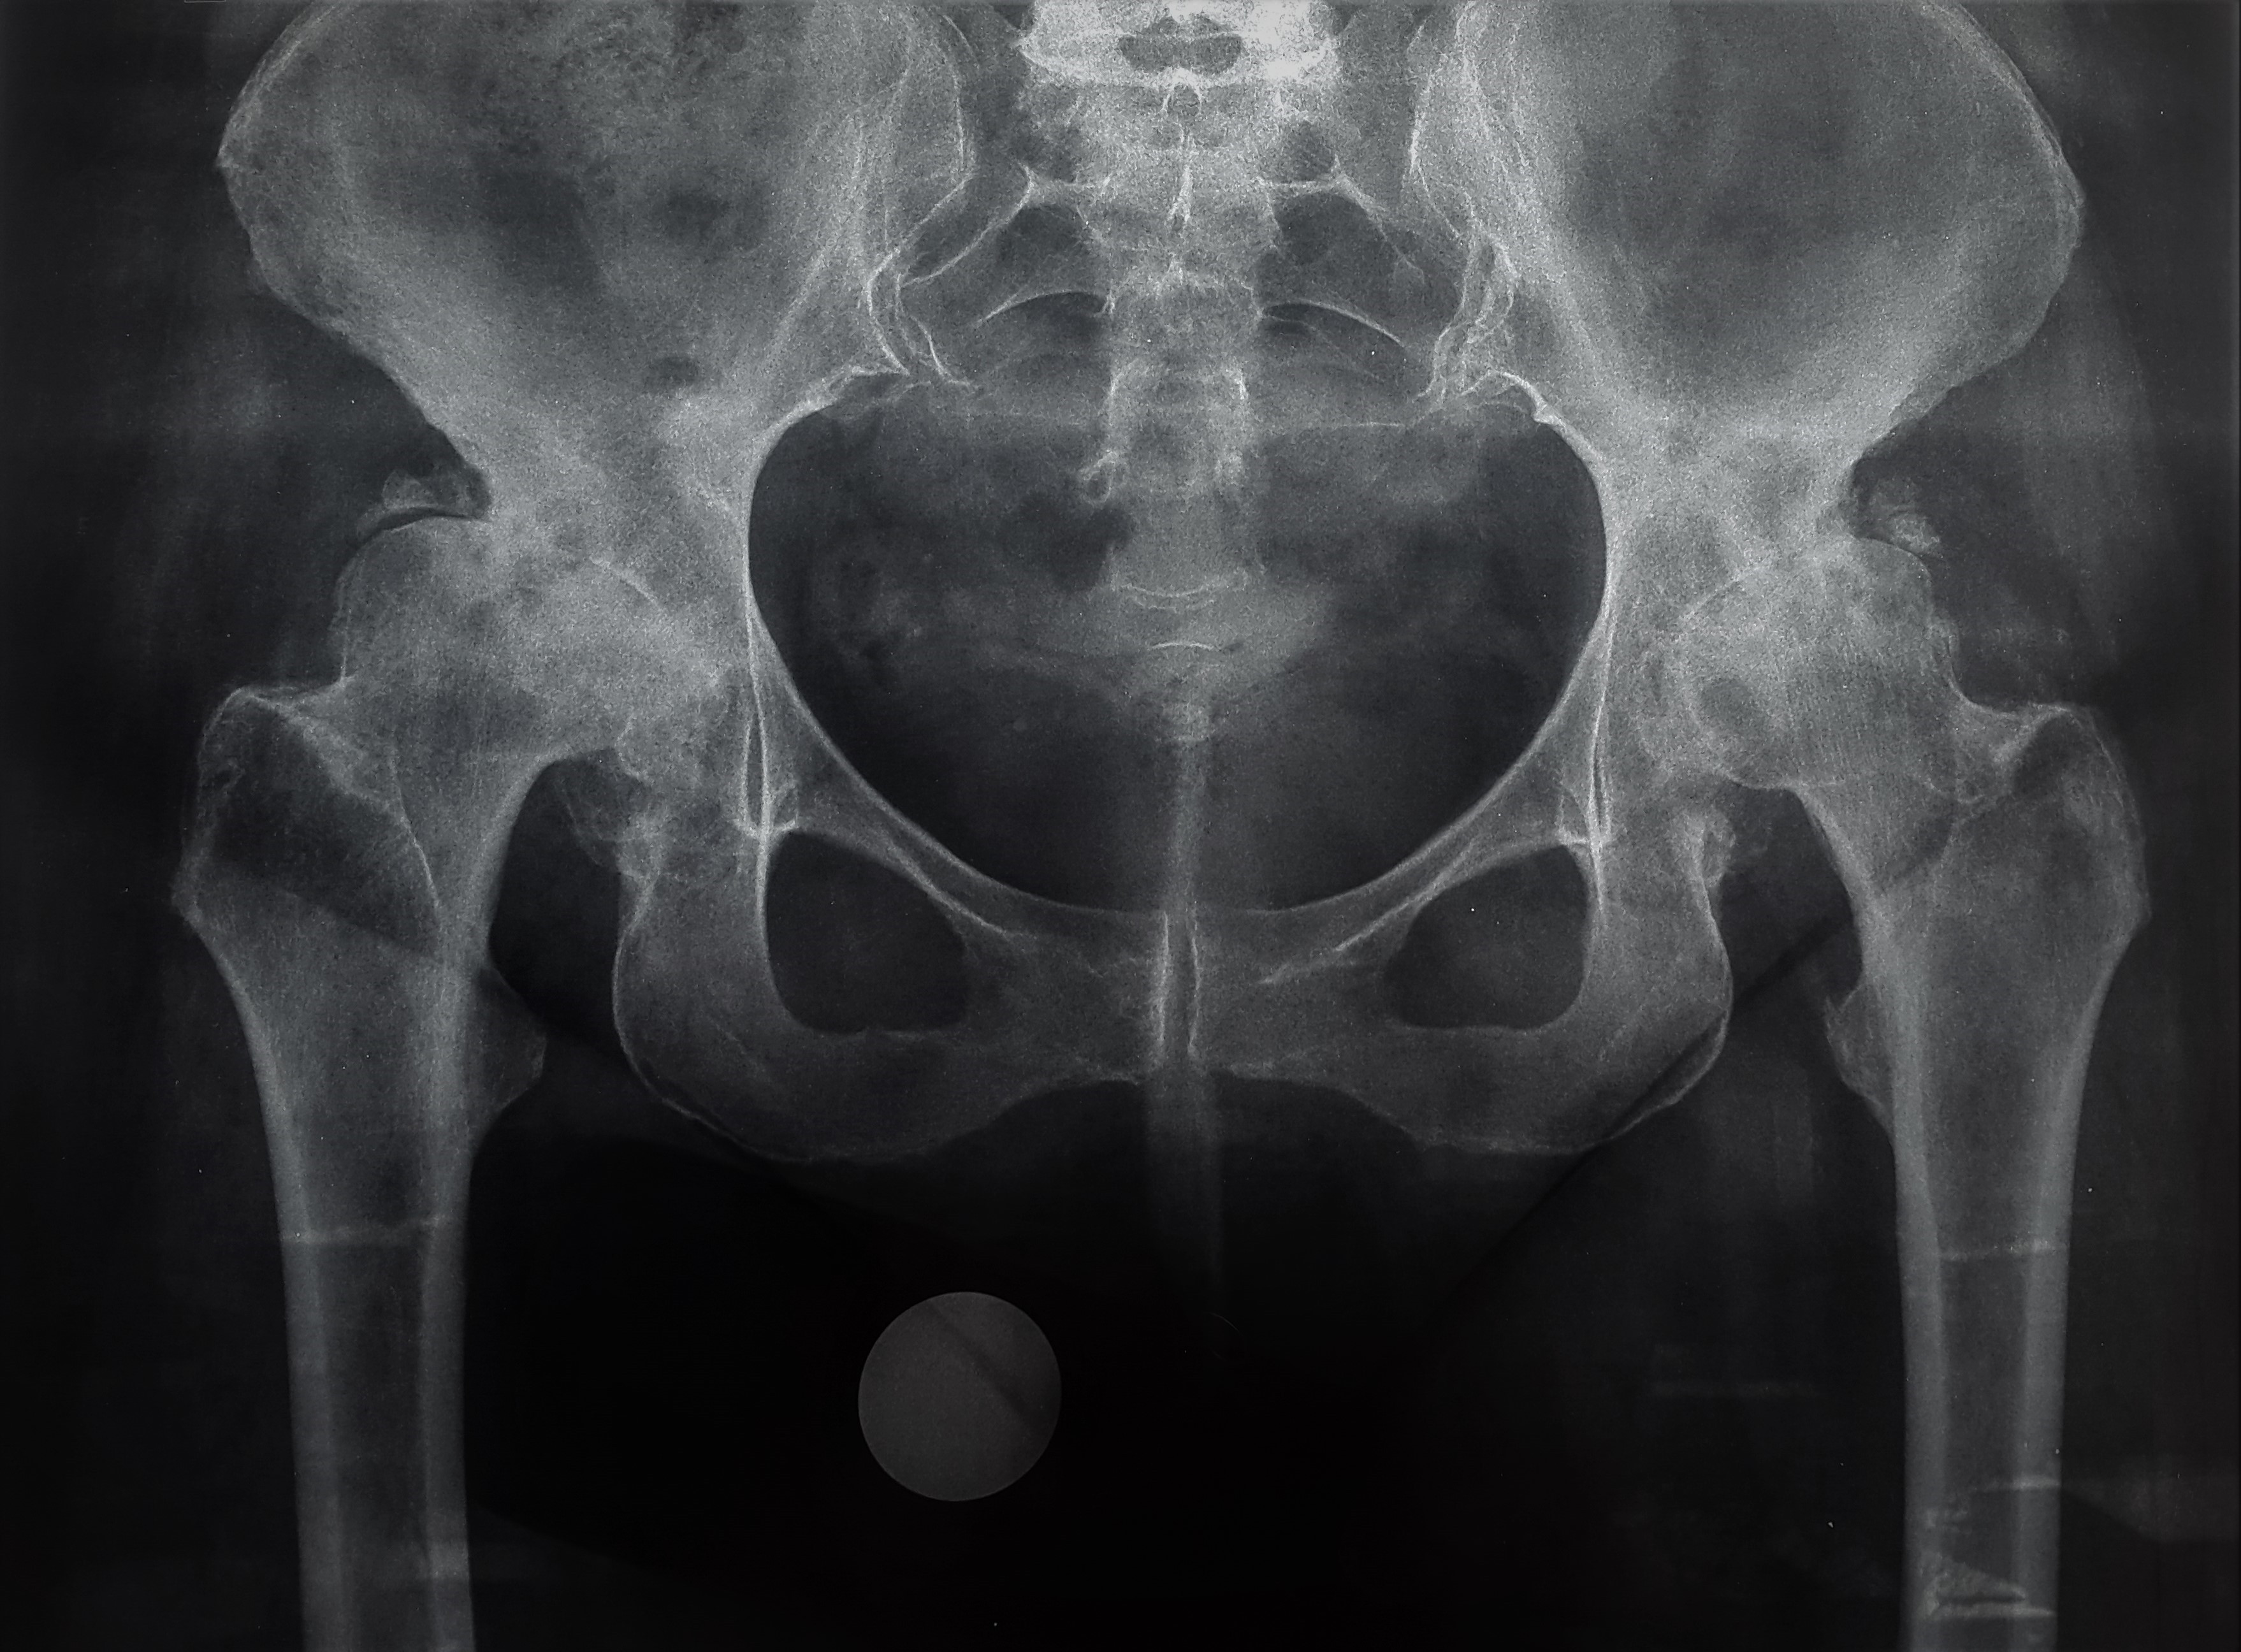

նկար 1․ Նախքան վիրահատությունը նկար 2․ Վիրահատությունից 7 տարի անց